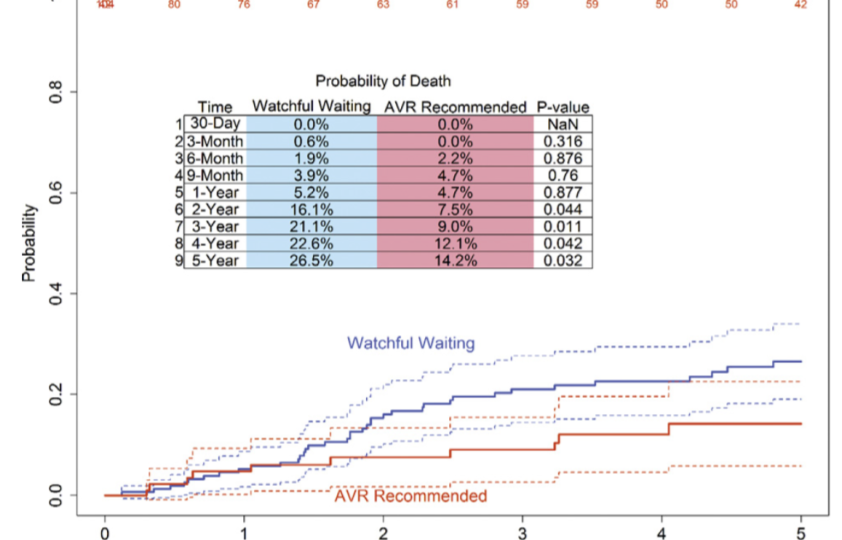

Em março de 2019, escrevi um texto neste mesmo blog falando sobre a viabilidade de realizar cirurgia cardíaca precoce em…

Os pacientes com estenose aórtica (EA) podem, didaticamente, ser divididos em dois grupos: com e sem sintomas. Os pacientes sem…